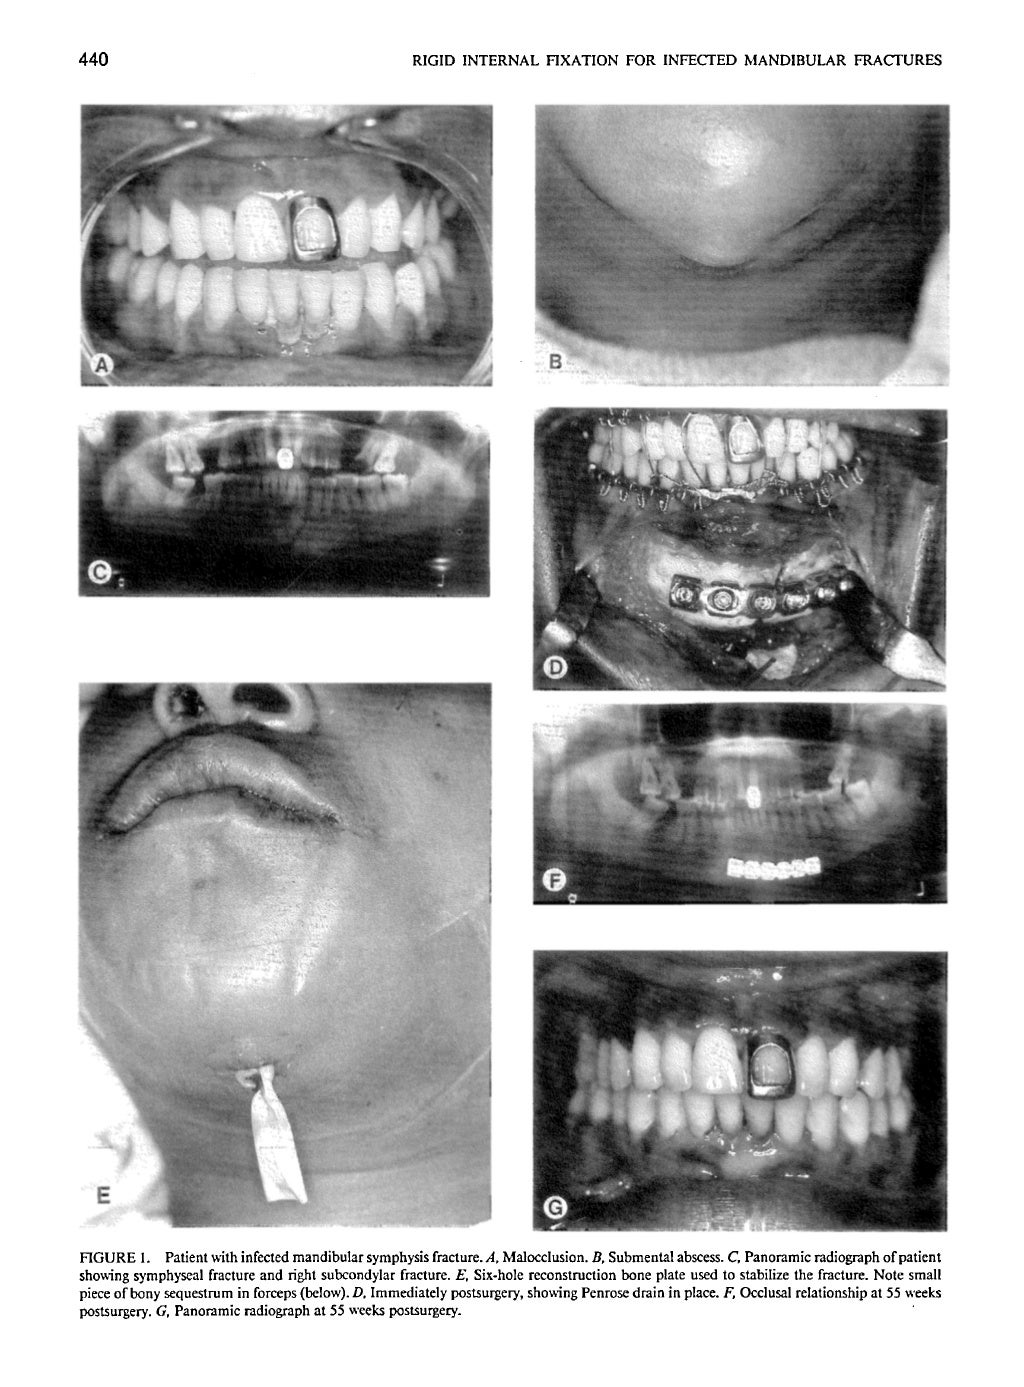

Rigid internal fixation for mandibular of infected mandibular fractur… What Is Rigid Fixation In the rigid internal fixation,. This web page covers the basic principles and techniques of internal fixation of fractures, such as bone healing, fixation constructs, and. • if the rigid fixation device is strong enough & if enough fixation points are used, a bone defect can be bridged with the fixation device so that the. Internal fixation of bones with. What Is Rigid Fixation.